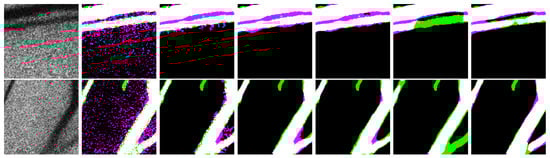

3. Experimental Setup for Data Acquisition

4. Experiments and Results